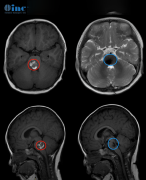

2020年3月,患者运动时突发头晕伴左侧下肢疼痛,脑干海绵状血管瘤卒中出血。 2021年8月,患者旅行时突然出现行走困难,右侧下肢行走时形态扭曲2021年12月,因再次出现行走困难,行...